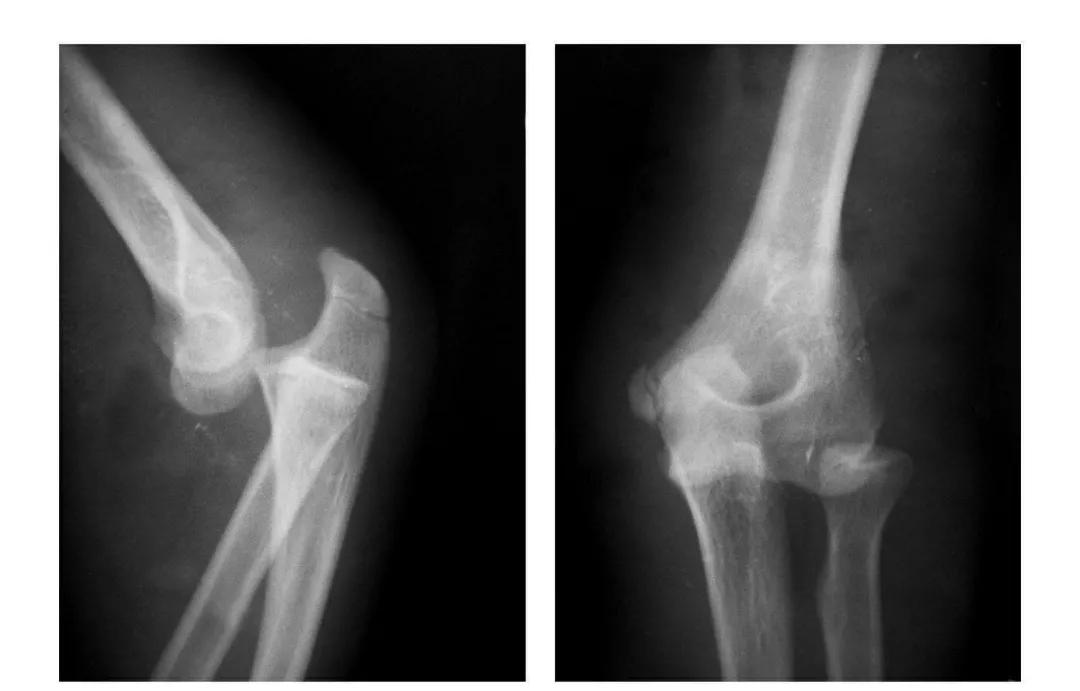

肘关节后脱位

例1:肘关节过伸性半脱位。

例2:肘关节过伸性半脱位并肱骨小头外缘骨折。

例3:肘关节后侧脱位。

例4:肘关节后外侧脱位。

例5:肘关节后内侧脱位合并滑车后缘骨折。

例6:肘关节后外侧脱位合并外髁劈裂骨折。

例7:肘关节后外侧脱位并桡骨头劈裂骨折,致肱骨小头将桡骨头骨块推向肘关节内前侧。

例8:肘关节后侧脱位并桡骨头外侧关节面骨折与尺骨冠状突骨折,致该骨块移向肘关节内下方。